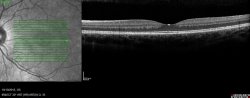

Qu'est-ce qu'un OCT ?

L’OCT (Optical Coherence Tomography) : un scanner de la rétine !

C’est un examen réalisé couramment au cabinet. En français, OCT est traduit par Tomographie en Cohérence Optique.

C’est un examen devenu incontournable pour l’évaluation des maladies de la rétine et qui permet d’obtenir des images en coupe très précises des différentes couches de la rétine.

Il peut être réalisé avec ou sans dilatation. Cependant un examen complet de la rétine nécessite en premier lieu un fond d’oeil avec dilatation pupillaire.

Il est demandé au patient de fixer un point au fond de l’appareil. Celui-ci balaye la rétine et réalise les images en coupes successives. L’acquisition de ces coupes prend quelques minutes.

Pendant l’examen, vous pouvez cligner, mais il faut garder la tête immobile sur la mentonnière pour que la machine reste alignée avec votre oeil.

C’est un examen totalement indolore et sans risque pour votre rétine.